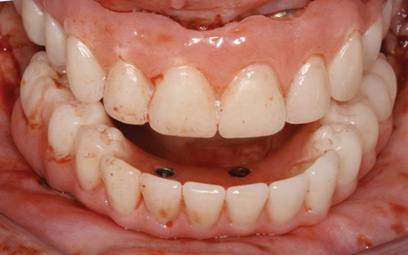

Fig 7. Existing dentition was sound periodontally and reasonably esthetic.

Figure 7

Fig 8. Failing dentition in an 82-year-old patient currently diagnosed with tardive dyskensia.

Figure 8

Interceptive implant therapy may then become a consideration earlier in life to create restorations that will not be subject to the latent effect of dental caries as aging continues. An example is shown in Figure 6 and Figure 7; the panoramic film of a 56-year-old man shows several orthognathic and extensive dental procedures historically. All full-coverage restorations had been replaced for a second time, and, again, all evidenced recurrent caries, but the existing dentition was periodontally sound and relatively esthetic.